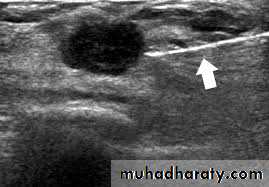

(2)ultrasound: ultrasound is particularly useful in young women with dense breasts in whom mammograms are difficult to interprets, and in distinguishing cysts from solid lesions. It also can be used to localize impalpable areas of breast pathology. It is useful as screening tool and remains operator dependent. Increasingly, ultrasound of the axillary tissue is performed when cancer is diagnosed and guided percutaneous biopsy of any suspicious glands may be performed.